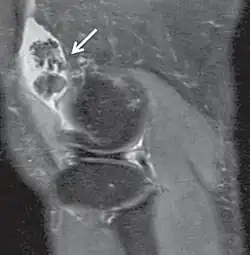

Proton density-weighted image of a knee with synovial chondromatosis

Proton density (PD)- weighted images are created by having a long repetition time (TR) and a short echo time (TE).[36] On images of the brain, this sequence has a more pronounced distinction between grey matter (bright) and white matter (darker grey), but with little contrast between brain and CSF.[36] It is very useful for the detection of arthropathy and injury.[37]